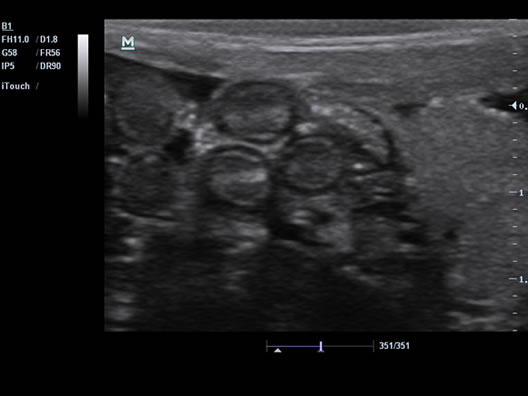

Performance

PSH™ (Phase Shift Harmonic Imaging)

The purified Harmonic Imaging for better contrast resolution provides clearer images with excellent resolution and less noise.

iClear™(Speckle Suppression Imaging)

Gain improved image quality based on auto structure detection.

-Sharper & Continuous Edges

-Smooth Uniform Tissues

-Cleaner ‘no echo areas’

iBeam™

Permits multiple scanned angles to form a single image, resulting in enhanced contrast resolution and improved visualization.

iTouch™

Gain instant auto image optimization in B, Color, and PW Modes with the click of a single key.